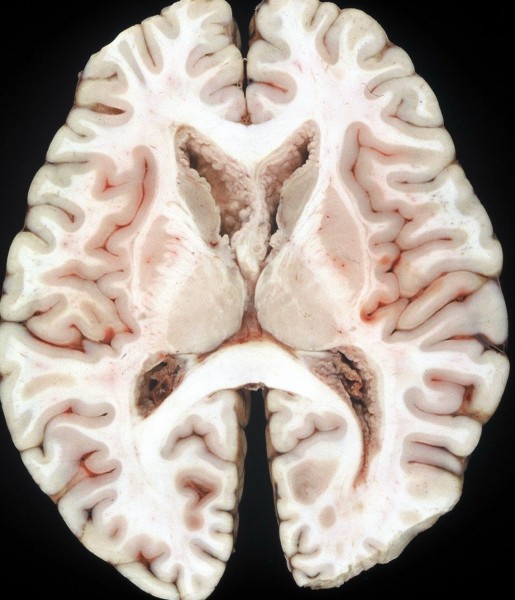

脳室上衣下浸潤(剖検例)

subependymal infiltration (autopsy)

1992年の剖検所見

大脳表面,脳幹部,脊髄くも膜下腔には腫瘍が見当たりませんが,側脳室を充満するように腫瘍が増殖しています。

側脳室壁に結節状の腫瘍が無数に認められます。これは今日では,内視鏡による脳室内観察で見ることができるものです。

上方が側脳室側です。脳との境にある脳室上衣 ependyumの下に腫瘍細胞が這うように浸潤しています。そこから血管周囲 Virchow-Robin spaceを通って脳深部に浸潤しています。

大脳深部(左)と小脳深部(右)には髄質血管に沿って浸潤します。これは髄芽腫などと同様の脳浸潤所見です。